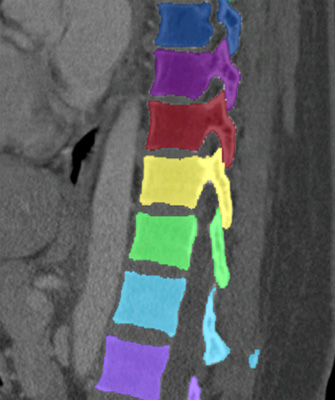

We trained and evaluated the method with five sets of CT and MR scans that visualize the spine. Reference segmentation masks for four of these datasets are publicly available, which allowed for a comparison with other publications that used the same data. Examples of images from the datasets are shown in Figure 3.

Similar performance was achieved for vertebra segmentation in various CT datasets with an average Dice score of and for vertebral body segmentation in an MR dataset with an average Dice score of . Surface distances were lower on CT images compared to MR images ( vs. ), however, there were also fewer training scans available in the MR dataset. Figure 4 illustrates the magnitude of differences of the automatic segmentations from the ground truth segmentations.

(a) Low-dose chest CT

(b) Lumbar spine CT (xVertSeg.v1 dataset)

(c) Lumbar spine MR

In the CT datasets, the segmentation was more accurate on high-resolution dedicated spine scans of healthy subjects compared with low-dose low-resolution chest CT scans and scans of subjects with in some cases severe compression fractures. This is also visible in the segmentation performance stratified by vertebra (Figure 5). Segmentations were more accurate for the lumbar (L1-L5) than for the thoracic vertebrae (T1-T12), which are covered by the more challenging low-dose chest CT scans. Outliers among the lumbar vertebrae correspond to vertebrae from the xVertSeg.v1 dataset, which features a number of severely deformed lumbar vertebrae that are particularly challenging to segment.